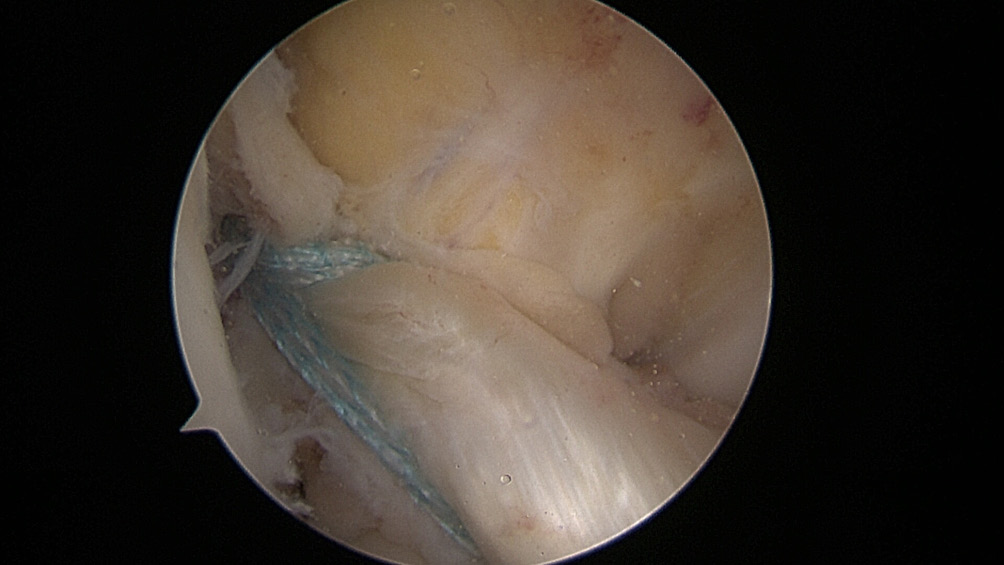

All the patients were operated on by the same team, using the same surgical technique and Neoligaments (Neoligaments) (Figure 1) or FiberTape (Biomet) (Figure 2) graft. It was fixed using Endobutton (Smith-Nephew, Watford, UK) on the femur and the interference screw, ComposiTCP30 (Biomet), on the tibia. It was prepared using the “outside-in” technique with the aimer device (Figure 3, Figure 4, Figure 5, Figure 6, Figure 7, Figure 8).